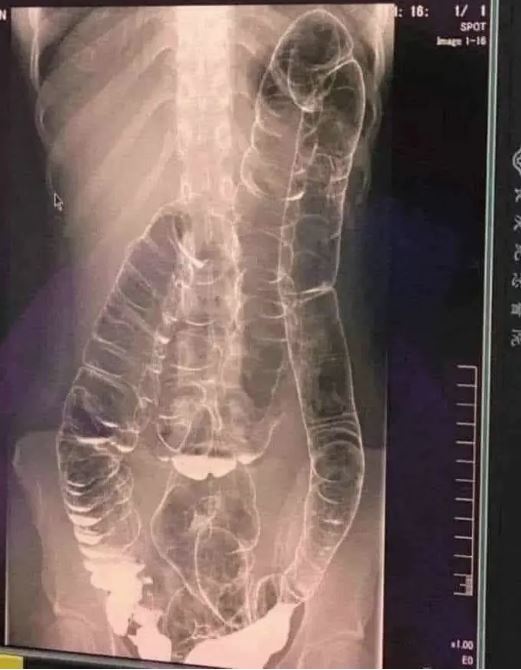

Chronic constipation is a common yet often overlooked condition. In extreme cases, prolonged constipation can lead to toxic megacolon, a life-threatening complication where the colon expands beyond its natural capacity, reaching the chest area and compressing vital organs like the heart.

When the colon is unable to expel waste properly, fecal matter accumulates, causing extreme bloating and distension. Over time, the colon loses its natural folds and ability to contract, resulting in:

- Severe bowel obstruction

- Bacterial overgrowth and toxin buildup

- Risk of colon rupture and sepsis